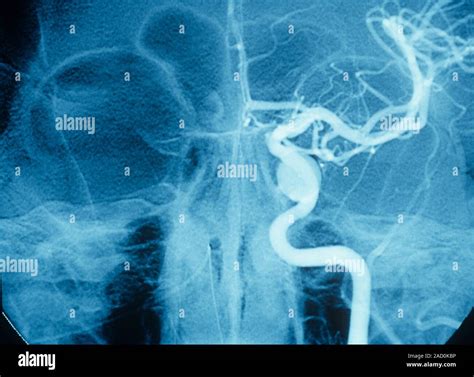

Diagnosing a Carotid Cavernous Fistula requires specialized imaging techniques to confirm the abnormal connection between the arteries and the venous sinus. Initial screenings often include:

• CT Angiography (CTA): Provides a high-resolution map of the vascular structures in the skull.

• Magnetic Resonance Imaging (MRI) and MRA: Useful for assessing the soft tissue and flow dynamics without ionizing radiation.

• Digital Subtraction Angiography (DSA): Considered the “gold standard” for diagnosis, this invasive procedure allows physicians to see the exact site of the fistula and plan for endovascular intervention.